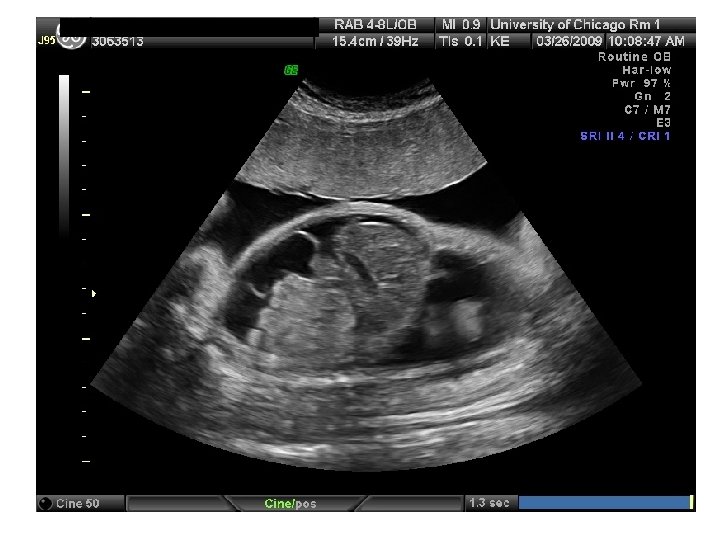

QUIZ What is Your Diagnosis? Case: Patient J. F. 30 years old, at 32 week gestation. Presented with the following pictures.

Answer: a) Trisomy 21 b) Non-immune Hydops c) Paravo virus Infection